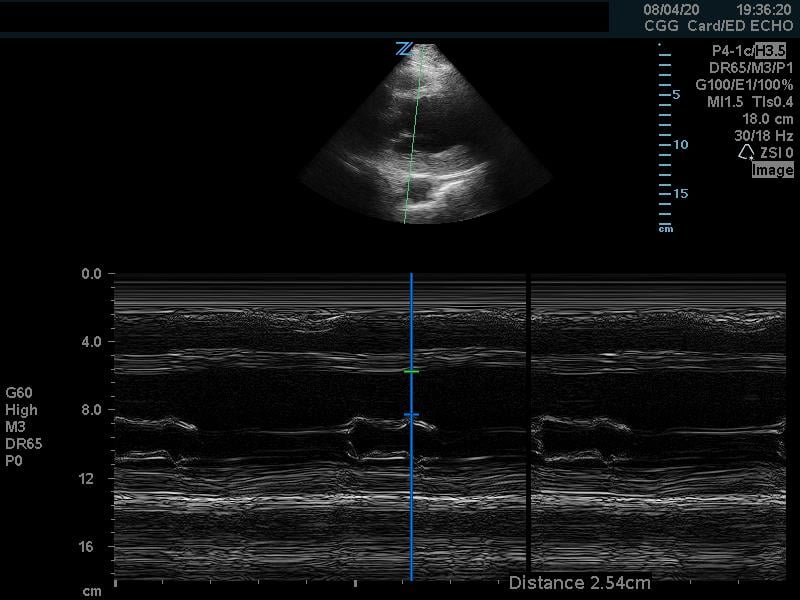

Fractional Shortening

Fractional shortening can be used to estimate EF. This is performed by placing an M-mode spike through the anterior and posterior walls of the LV at the mid-LV in the parasternal short axis view. In M-mode, the diameter of the left ventricular cavity is measured in end-diastole (LVEDD) and end-systole (LVESD). One can then apply the below formula to obtain an estimation of EF%:

FS = (LVEDD-LVESD/LVEDD) x 100%

A normal EF is suggested by a percent FS between 25-45%. (Fig. 7,8)13

Figure 7. Fractional shortening measurement obtained using M-mode, indicating LV systolic function within normal range

Figure 8. Parasternal short axis view at the mid-papillary level with fractional shortening measurement obtained using M-mode. Fractional shortening value of 19.6%, indicating hypodynamic LV systolic function.